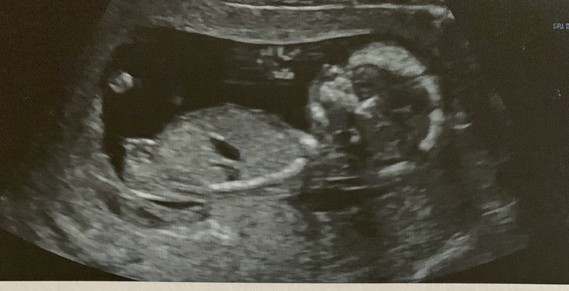

Sentir bebe 14 sa

Sentir bebe 14 saのギャラリー